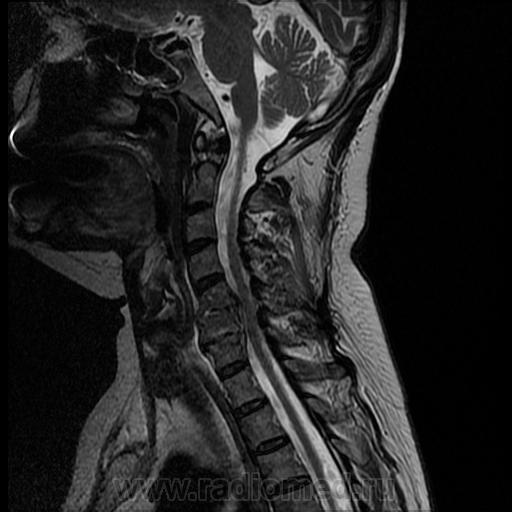

Кроме этого, для выявления полной картины потребуется рентгенография в нескольких проекциях шейного отдела, компьютерная томография или МРТ. После проведения полного обследования назначается адекватная терапия.

Грыжа межпозвоночных дисков

Эта патология представляет собой выдавливание диска в позвоночный канал. Если хрустит шея по этой причине, то по возрасту пациенты укладываются в диапазон от 25 до 50 лет. В пожилом возрасте грыжа встречается исчезающе редко в связи с тем, что позвоночный диск с годами теряет подвижность, а потому «соскочить» с места физически не способен.

Причины развития грыжи межпозвоночного диска:

- травматическое воздействие. Чаще всего – падение на спину или ощутимый удар в верхнюю часть туловища сзади;

- повышенная нагрузка: к примеру, подъем с земли тяжелых предметов. Поэтому довольно часто грыжа диагностируется у тяжелоатлетов, грузчиков;

- избыток массы тела;

- искривления позвоночника разной этимологии и степени запущенности;

- резкий поворот головы со значительной амплитудой.

И опять-таки остеохондроз. Треть пациентов с таким диагнозом при недостаточном или непрофессиональном лечении в качестве осложнения получают грыжу.

При этом заболевании боль возникает во время поворота головы, имеет высокую интенсивность, отдается в руку. Могут также наблюдаться проблемы с кистью руки: онемение, «мурашки» по коже, снижение чувствительности конечности.

Анализы мочи и крови в случае, когда наблюдается хруст в шейном отделе позвоночника, обычно малоинформативны. Однако и они могут прийтись кстати, поскольку отражают наличие воспалительного процесса и косвенно указывают на развитие патологий. Из инструментальных обследований наиболее ценны:

- рентгенография шейного отдела. Обычно снимок делается с двух ракурсов;

- магнитно-резонансная и/или компьютерная томография;